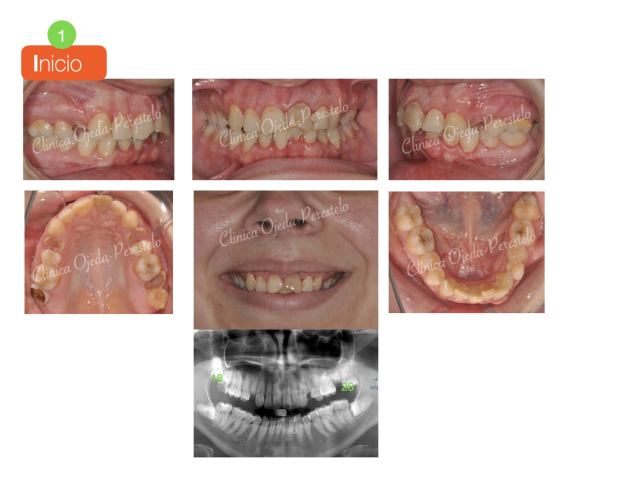

Apiñamiento severo con molares con mal pronóstico Casos de Éxito - Adultos